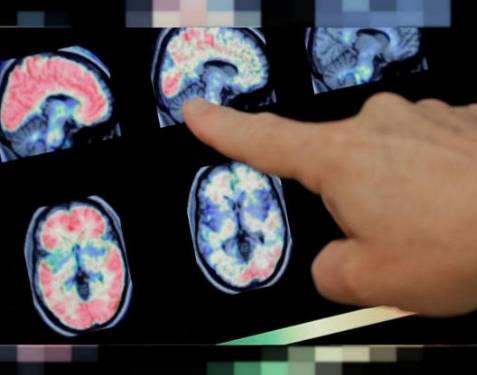

عضو هیات علمی دانشگاه علوم پزشکی تهران گفت: هرچند در بیماران کرونایی شیوع تظاهرات عصبی کمتر از عوارض تنفسی است، اما تظاهرات عصبی از جمله سکته مغزی در سیر بیماری یا به عنوان یکی از عوارض بیماری کرونا میتواند، بروز کند.

دکتر محمودرضا اشرفی اظهار داشت: بی حرکتی، شدت بیماری، کمبود اکسیژن و التهاب از جمله عواملی هستند که عروق بیماران کرونایی را مستعد ترومبوز میکنند و اگر ترومبوز شریانی باشد، سبب سکته مغزی میشود.

وی در گفتگو با ایرنا با اشاره به اینکه مبتلایان به کرونا در معرض ابتلا به ترومبوز و لخته شدن خون هستند که این موارد هم میتواند در وریدها و هم در شریانها باشد، گفت: اگر این موضوع در وردیدها رخ دهد، سبب آمبولی ریه و در صورت بروز در شریانهای عصبی سبب سکته مغزی میشود.

وی با اشاره به اینکه تظاهرات عصبی در مبتلایان به کرونا گزارش شده است، افزود: ویروس کرونا تمایل دارد سیستم عصبی را هم درگیر کند و مهمترین راه ورود به سیستم عصبی بدن از راه عصب بویایی است.

وی بیان داشت: تشنج، کاهش سطح هوشیاری، سکتههای مغزی، بیماریهای عصبی عضلانی مانند گیلن باره، فلج عصبهای چشم، از جمله علایم بیماری کرونا است که تاکنون گزارش شده است.